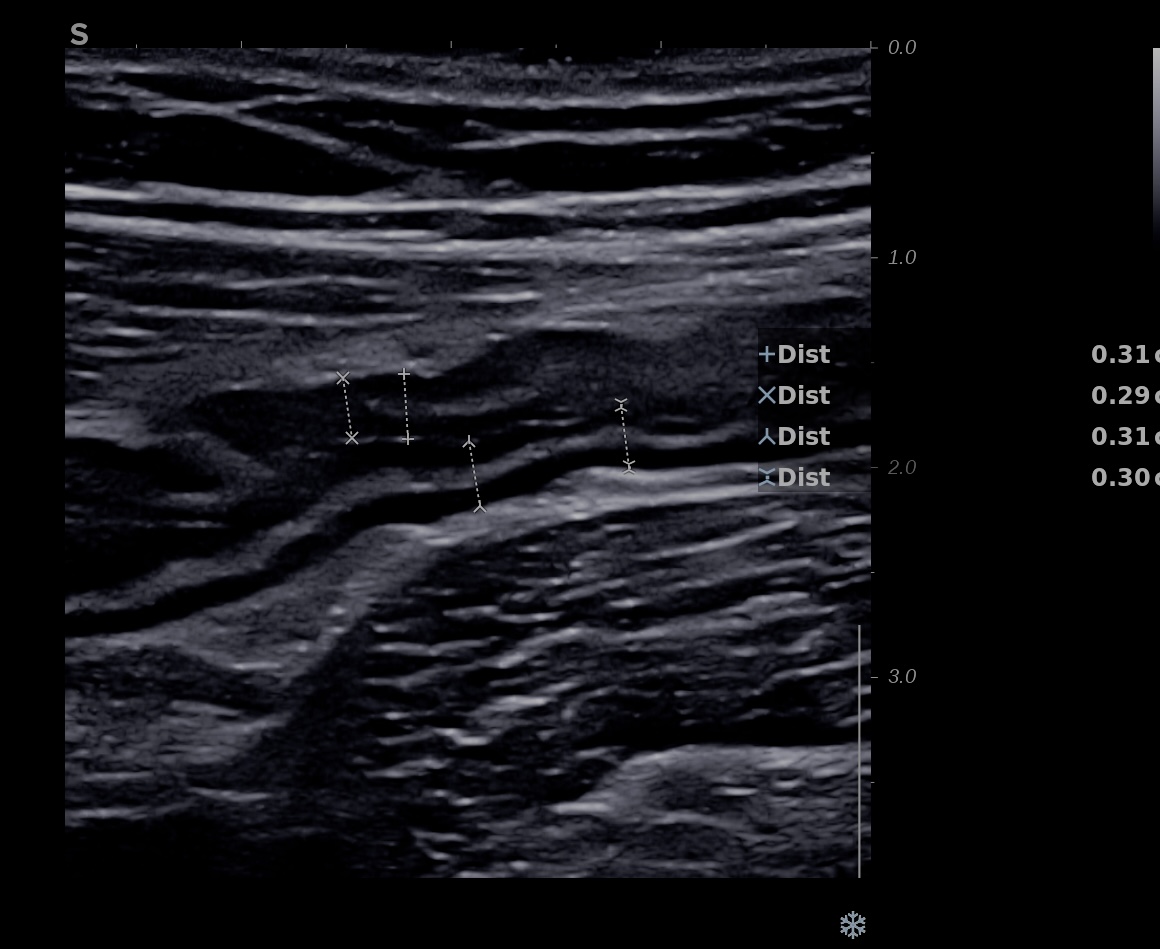

Epaississement entre 4.5 et 7 mm selon les segment, la structure en couche disparait totalement par endroit, à d’autre elle est partiellement conservée. Activité doppler intense de la paroi

Le Score de Milan (MUC) est à (1,4 x7+2) = 11,8

Là encore la paroi est très hypoéchogène, la structure en couches est par endroit totalement absente, ulcérations en surface, infiltration de la graisse, doppler intense, petites adénopathies périphériques.

Le rectum est bien vu avec la sonde basse fréquence la paroi atteint 10 mm à ce niveau.

Le score de Milan MUC est de (10 x1,4+2) = 16